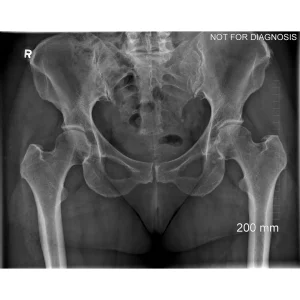

A total hip replacement (also called total hip arthroplasty) is a surgical procedure in which a damaged or worn hip joint is replaced with artificial components. The hip is a ball-and-socket joint, meaning the ball at the top of the thigh bone sits in a socket on the pelvis. During surgery, the damaged ball (femoral head) is replaced with a metal or ceramic ball attached to a stem, and the damaged socket is replaced with a metal cup lined with plastic, ceramic, or metal.

Hip damage caused by conditions such as:

- Osteoarthritis (most common)

- Rheumatoid arthritis

- Avascular necrosis (loss of blood supply to the hip bone)

- Hip fracture or trauma

- Congenital or developmental hip disorders

Osteoarthritis (most common)

Rheumatoid arthritis

Avascular necrosis (loss of blood supply to the hip bone)

Hip fracture or trauma

Congenital or developmental hip disorders